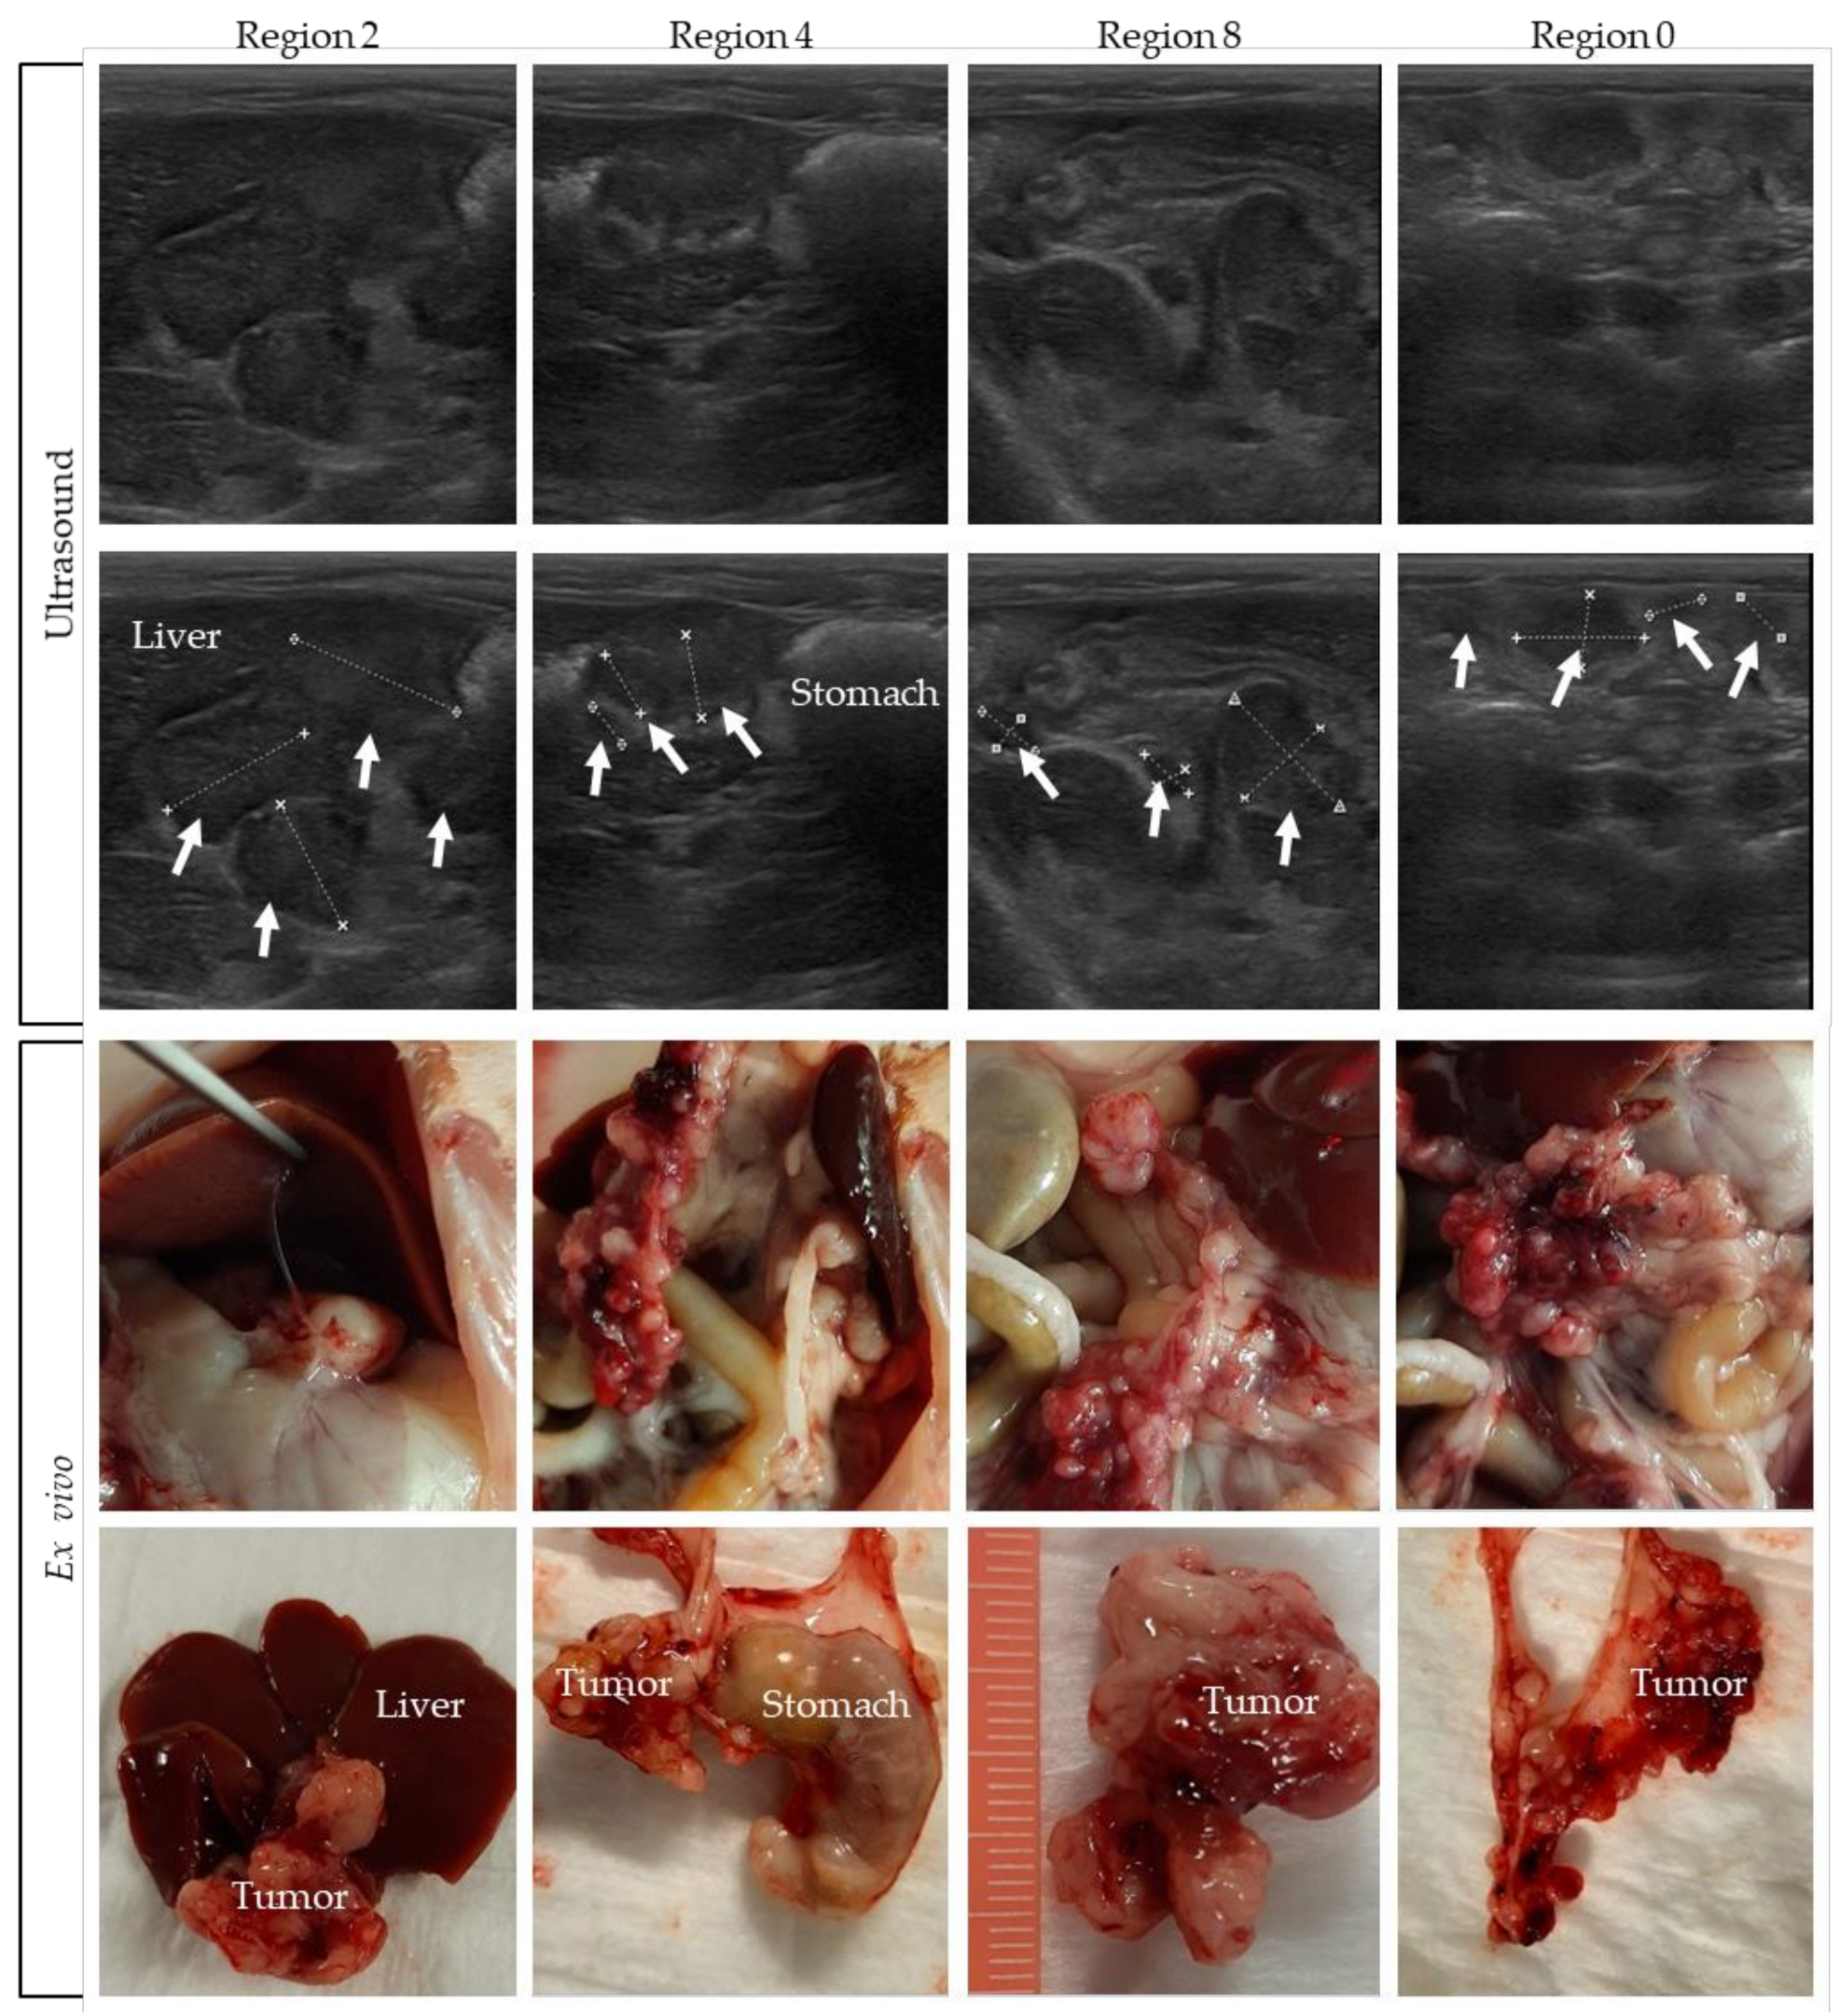

3.3. Comparing Ultrasound Pictures with the Ex Vivo Tumor Load

Pictures were taken and tumor size was measured during the dissection of the rats. In Figure 6, pictures of rat 4 are compared with the corresponding ultrasound indication of four different regions. In the upper panel of the figure, ultrasound pictures are shown, with the tumors indicated in the second row of pictures. The ex vivo pictures are presented in the lower panel. In Supplementary Figure S4, tumor images on ultrasound are compared to the ex vivo tumor load of the other rats.

Figure 6.

Tumors on ultrasound compared to the ex vivo tumor load. Tumor lesions are indicated with white arrows, and organs are named.

Comparing the ex vivo tumor size of all individual tumors in a specific region with ultrasound-based size measurements is very difficult, especially for the many smaller lesions. On ultrasound only, part of the tumor load is visible, which makes it difficult to compare it with the exact same region ex vivo. Nevertheless, these figures show that, overall, a very accurate tumor assessment can be performed on ultrasound.